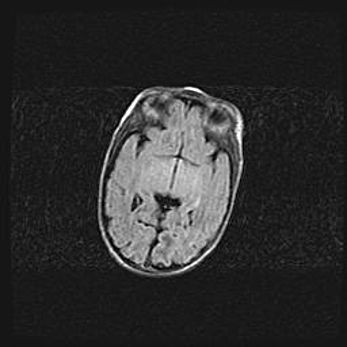

Сообщающаяся гидроцефалия. Кистозная энцефаломаляция головного мозга.

Возраст: 3 месяца 4 дня

Вес: 3100 г

Пол: женский

Окружность головы: 34 см

Срок гестации: 31 неделя

Кистозная энцефаломаляция головного мозга - одна из форм поражения головного мозга в детском возрасте. Характеризуется возникновением множественных и распространённых кист в коре, белом веществе и подкорковых образованиях головного мозга у плодов, новорождённых и детей раннего возраста. Развитие кистозной энцефаломаляции связано с внутриутробной асфиксией и гипотонией, родовой травмой, тромбозом синусов, пороками развития сосудов, инфекциями, сепсисом и другими причинами. Наиболее значимые инфекционные агенты: вирусы простого герпеса, цитомегалии, краснухи, токсоплазмы, энтеробактерии, золотистый стафилококк и другие.